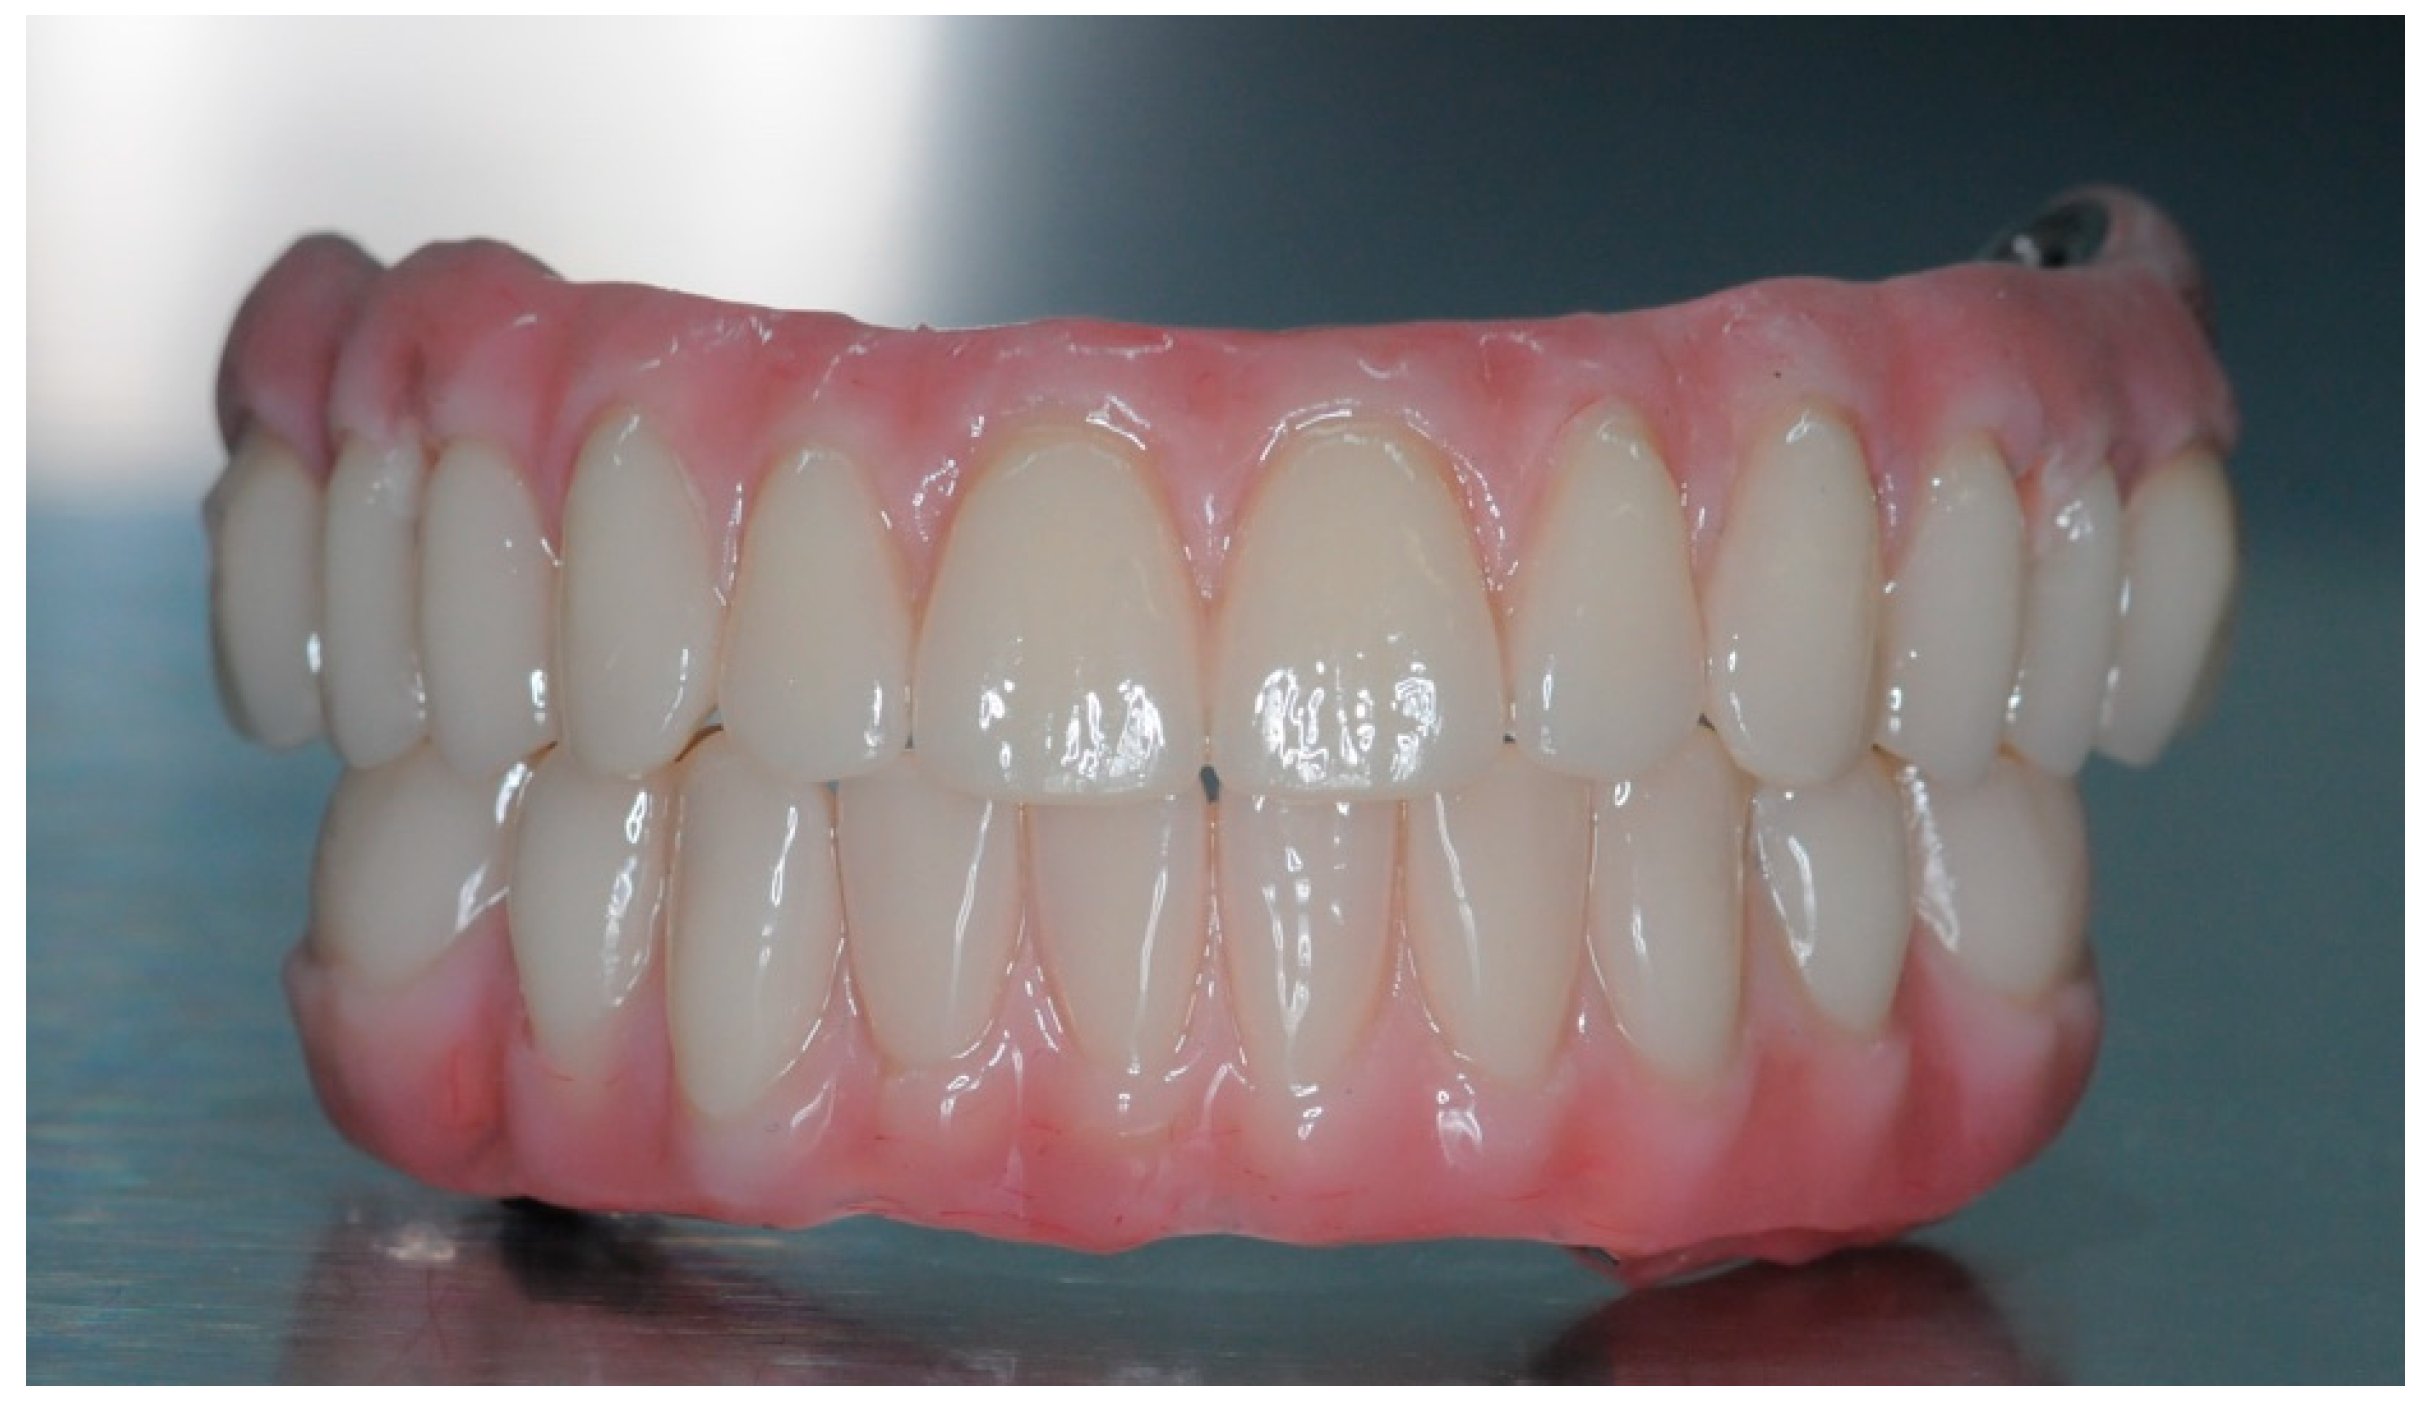

2.5. Final Prosthesis

3.5. Function and Aesthetics